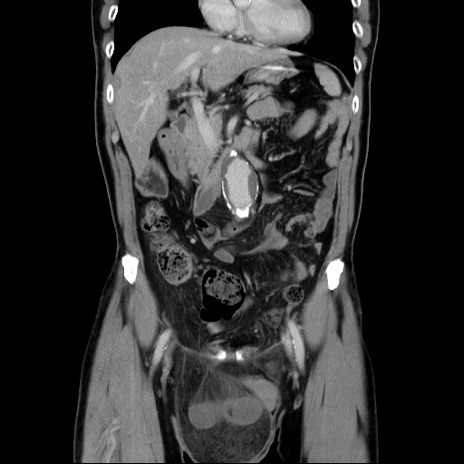

症例34(冠状断像)

【症例】60歳代 男性

【主訴】右鼠径部膨隆

【現病歴】1年程前より右鼠径部膨隆あり。自己にて還納可能だったため放置していた。3時間前より右鼠径部の脱出を認め、還納困難となり受診。

【身体所見】右鼠径部に小児頭大の膨隆あり。弾性硬であり、用手還納は困難。左鼠径部にも膨隆を認める。脱出はなし。